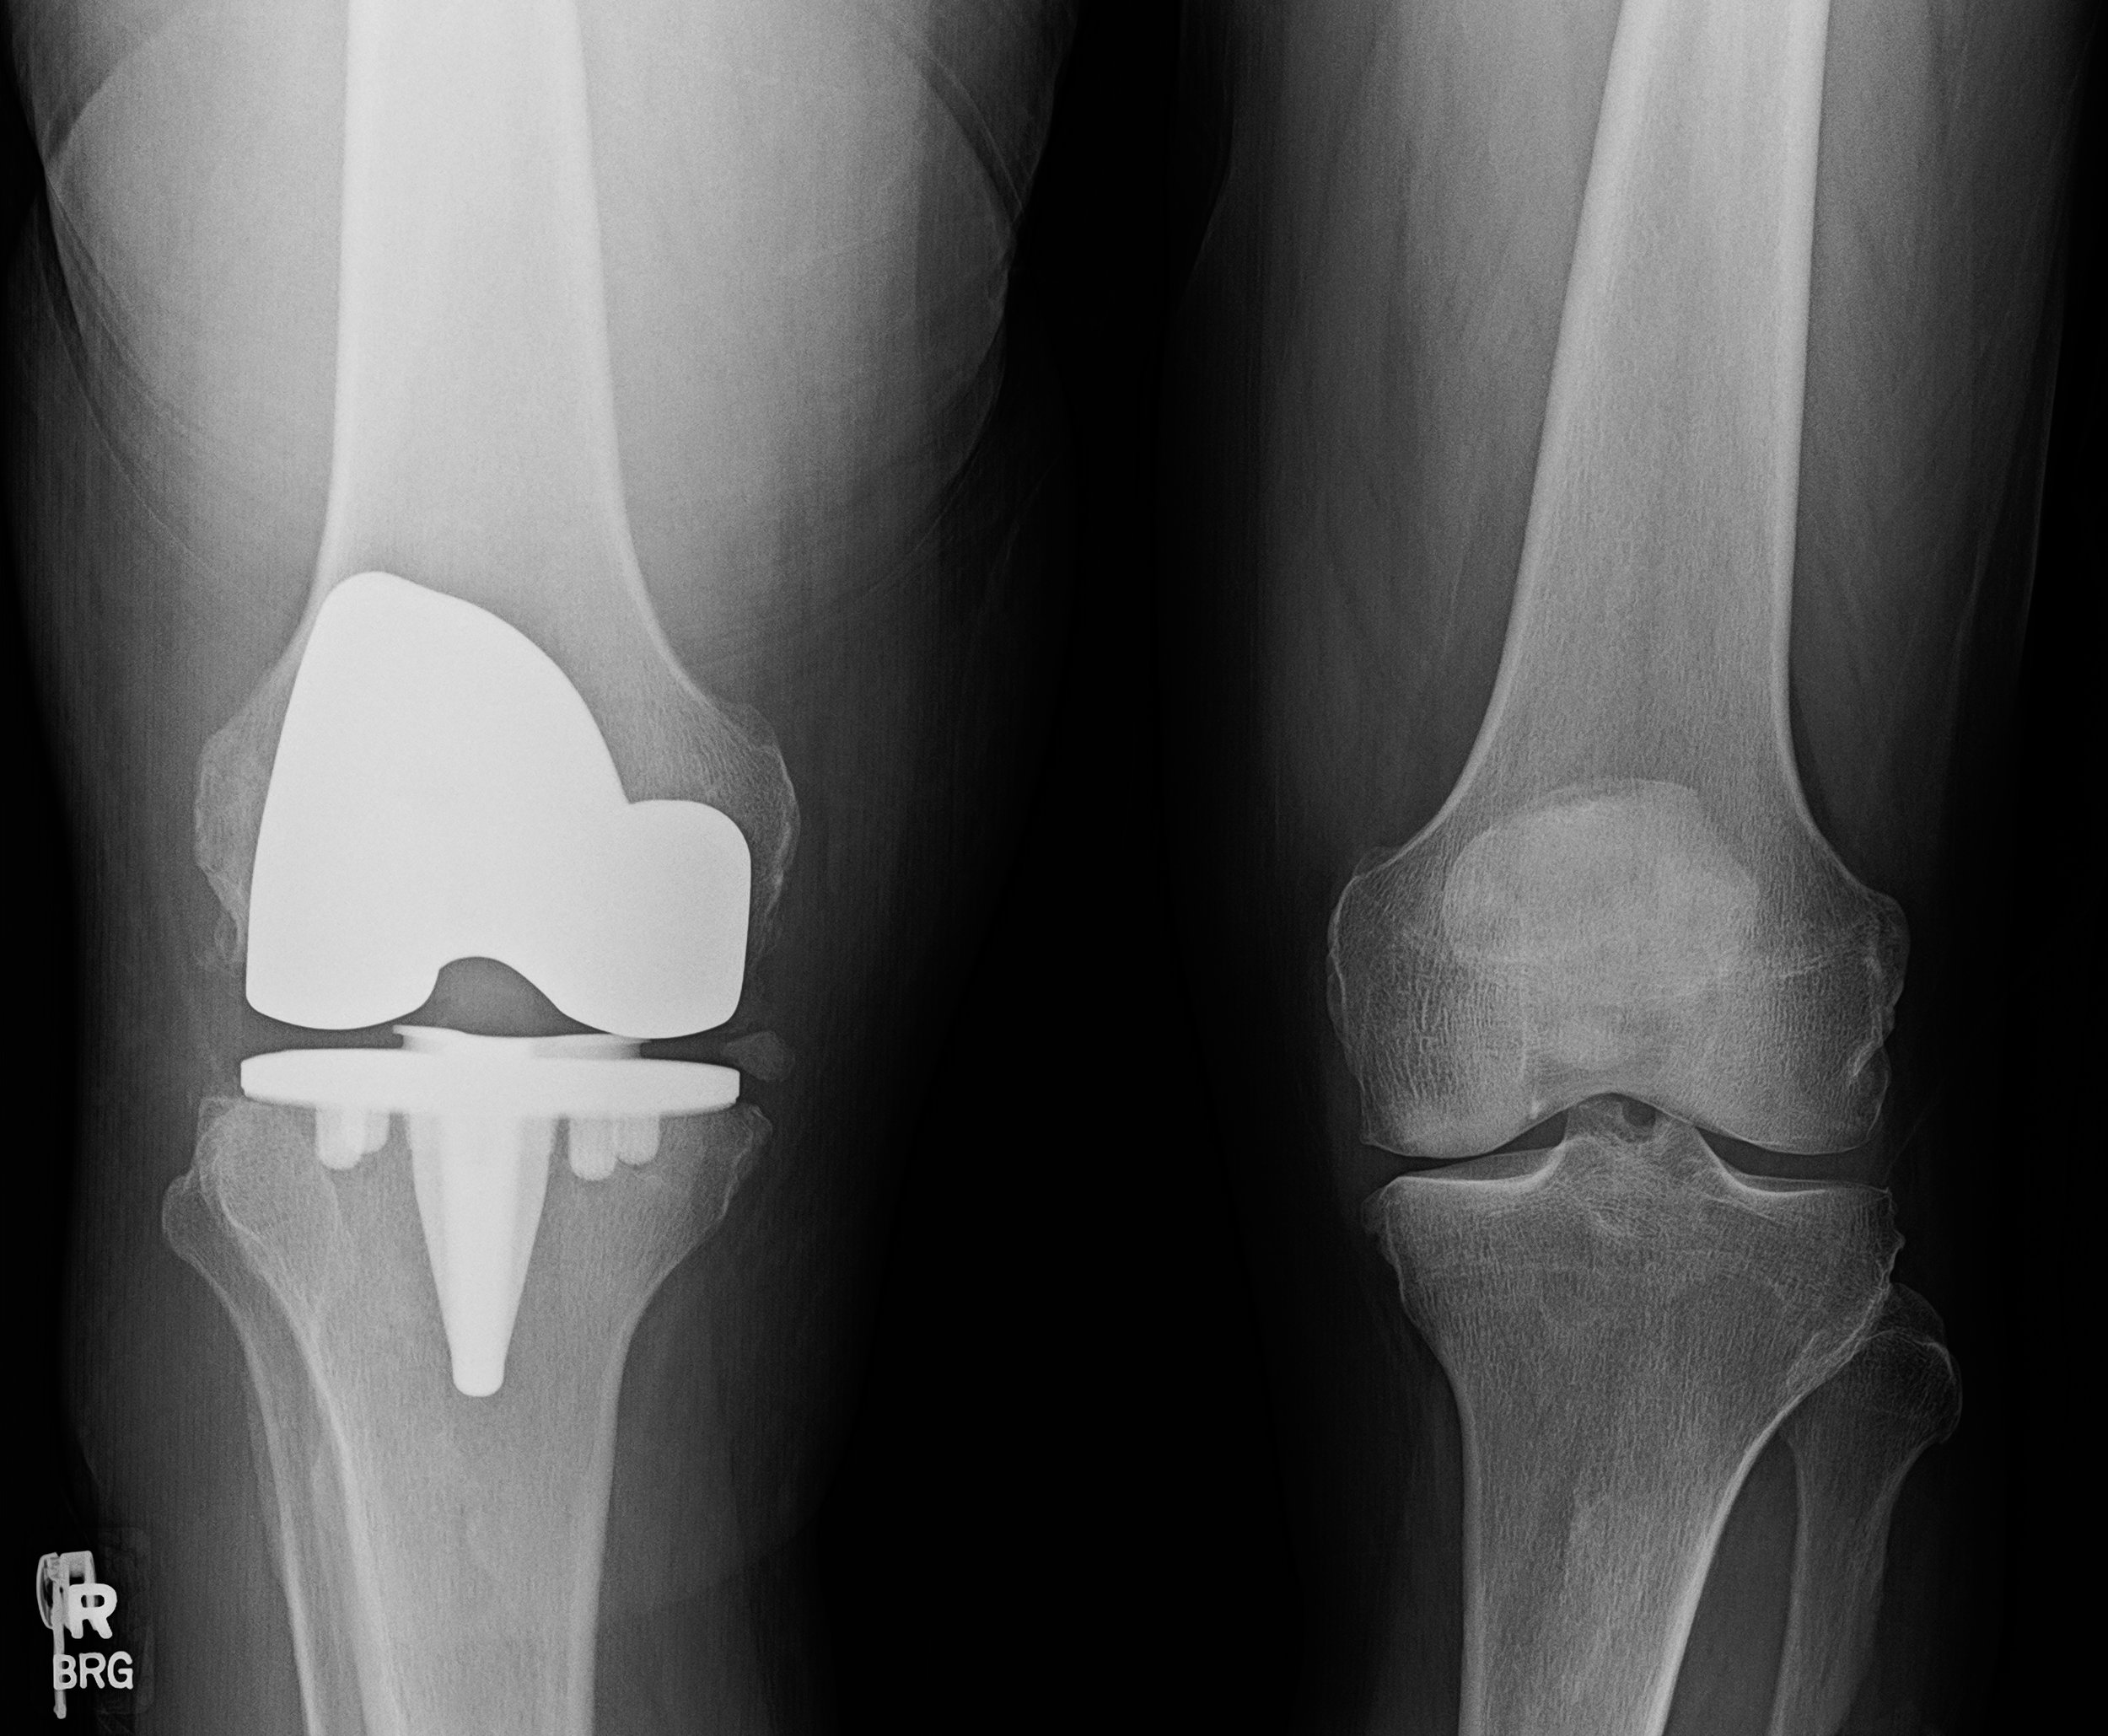

Partial vs Total Knee Replacement: Which Is Right for You?

Partial and total knee replacement treat different patterns of arthritis. Learn how they compare and which option may be appropriate based on your knee condition.